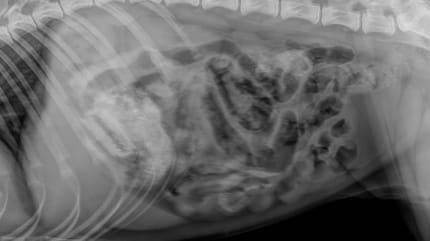

Röntgenbild Giftköder mit Rasierklinge

© Tierklinik Posthausen / Facebook

Der Hundehalter ist völlig arglos, als die Hündin etwas auf dem Boden entdeckt und gierig verschlingt. Ein Röntgenbild in der Tierklinik bringt schließlich die erschütternde Wahrheit ans Licht!

Denn im Inneren der Mahlzeit lauert eine tödliche Gefahr, wie sich beim Röntgen herausstellt. Eine Rasierklinge hatte sich im Magen des Hundes festgesetzt! Wenige Stunden später musste sie in der Tierklinik in Posthausen notoperiert werden.